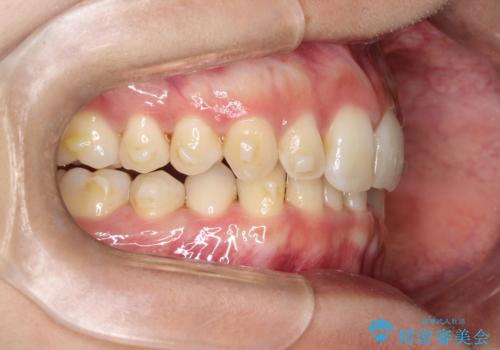

ディープバイト改善のためのインビザライン治療

- 患者様は、全体的な歯列のガタガタとディープバイト(深い噛み合わせ)を主訴として来院されました。診断の結果、ディープバイトを改善するためには、歯列全体の拡大が必要であると判断しました。治療には、透明なマウスピース型矯正装置「インビザライン」を使用し、歯を適切に拡大しながら歯並びを整える計画を立てました。治療期間はおおよそ2年を見込んで進め、最終的に見た目にも大きく変化をもたらすことを目指しました。

ディープバイトの治療には、奥歯の高さや前歯の位置に対する繊細な調整が必要です。本症例では、インビザラインによる歯列拡大を行うことで、噛み合わせを改善し、歯並び全体を整えました。治療過程では、歯間のスペースを確保するため、IPR(インタープロキシマルリダクション)を適宜行い、無理なく歯列の調整を行いました。治療後は、歯並びが大きく改善され、患者様の見た目にも大きな変化が現れました。インビザラインは透明で目立たず、治療中の見た目を気にされる患者様にも配慮した治療法です。